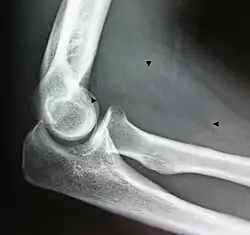

- Resection of an intermuscular lipoma in the elbow region

-

Intraoperative photo -

Operating field after removal of the lipoma: Arrow marks the median nerve that was compressed by the lipoma. -

The resected lipoma

(8 cm × 6 cm × 3 cm)